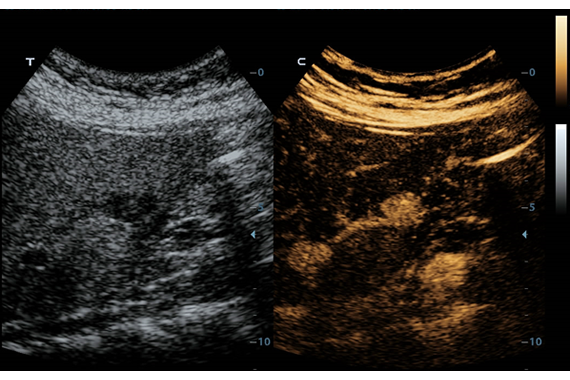

• PSH™ - технология гармонической визуализации с фазовой инверсией.

• Echo Boost™ - режим улучшенной визуализации для кардиологии.

Одним из ключевых преимуществ DC-60 EXP X-INSIGHT является технология формирования УЗ-луча. Она дополняет основной луч параллельно эхо-сигналами, что приводит к получению более мощного сигнала и изображений высокого качества с помощью систем iLive, iPage, Smart OB, Smart NT.